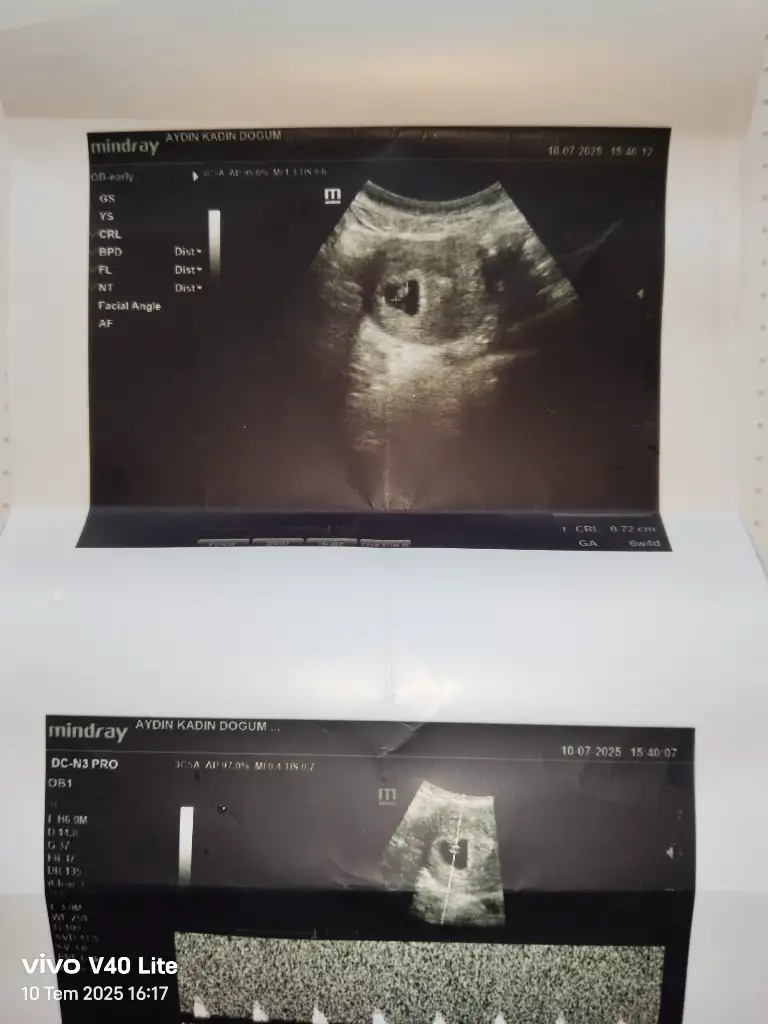

Sizce benim nedir 6+4Kız bence

Sizce benim nedir 6+4